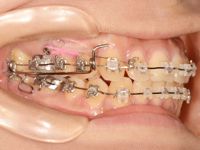

調整前の写真がこちらです![]()

写真では分かりづらいのですが、上顎の1番奥の歯と奥から2番目の歯の間に、舌先で触っても分かるくらいの隙間が出来てきました![]()

![]()

もう綺麗に並んでいるように見えますが、奥歯の咬み合わせを見ると、まだ少し上顎の方が前に出ていて、出っ歯気味です![]()